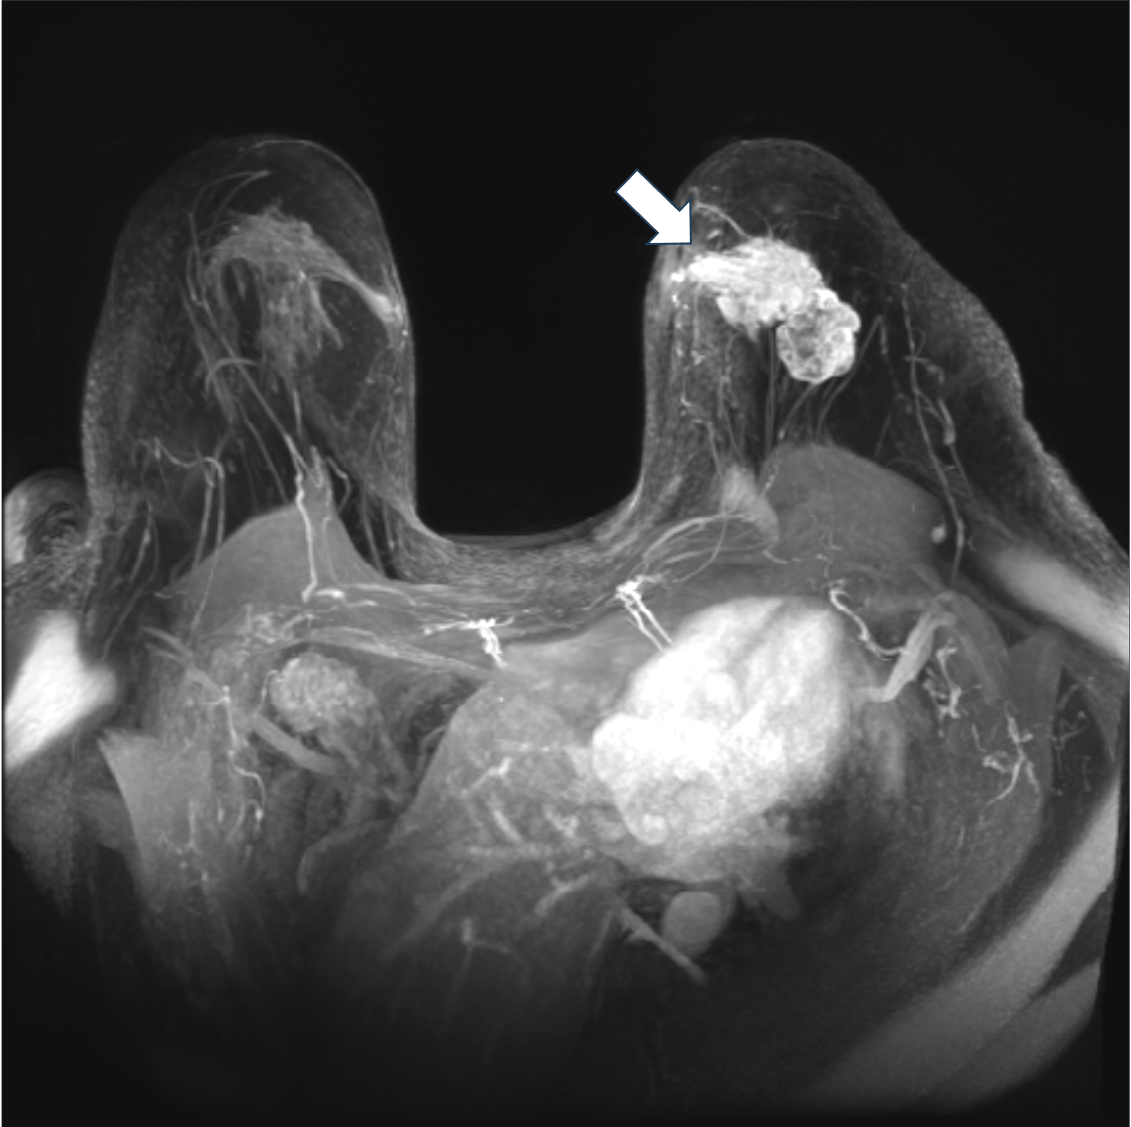

6. ダイナミックMRI 早期相 MIP像

左乳房に不整形腫瘤を認める。MIP像は一目で病変全体を把握することができる。MIP像でも乳頭側の造影効果が強いことが分かる。